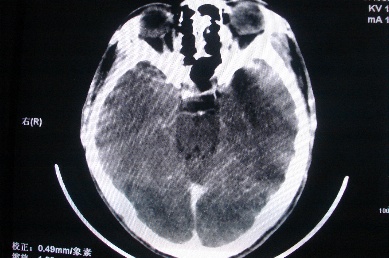

以下是引用zhangzhongshou在2007-4-18 17:49:00的发言:[br]脑实质内多发高密度结节影,支持肉芽肿得诊断,究竟是结核性、真菌性或寄生虫性的需结合临床,进一步检查确诊,但从影像上无法鉴别,只是临床上结核性肉芽肿最为多见而已。